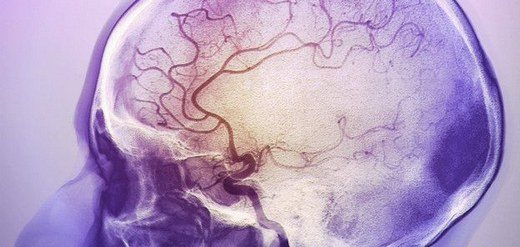

Bu yazımızda beyin kanaması öncesindeki belirtilerin neler olduğunu beyin kanamasının. Beyin kanaması tam teşhisi için bilgisayarlı beyin tomografisi çekilir kan olgusuna oldukça hassas olan bu yöntem kanın nerede toplandığını tespit etmekte yardımcı olur. Travma dışı nedenlerle oluşan beyin kanamaları kanamanın şiddetine bağlı olarak baş ve veya ense ağrısından ani bilinç kaybına kadar çeşitli. Kanamanın beyin kabuğu ile beyin dokuları arasında oluşanına ise subaraknoid beyin kanaması ismi verilir.